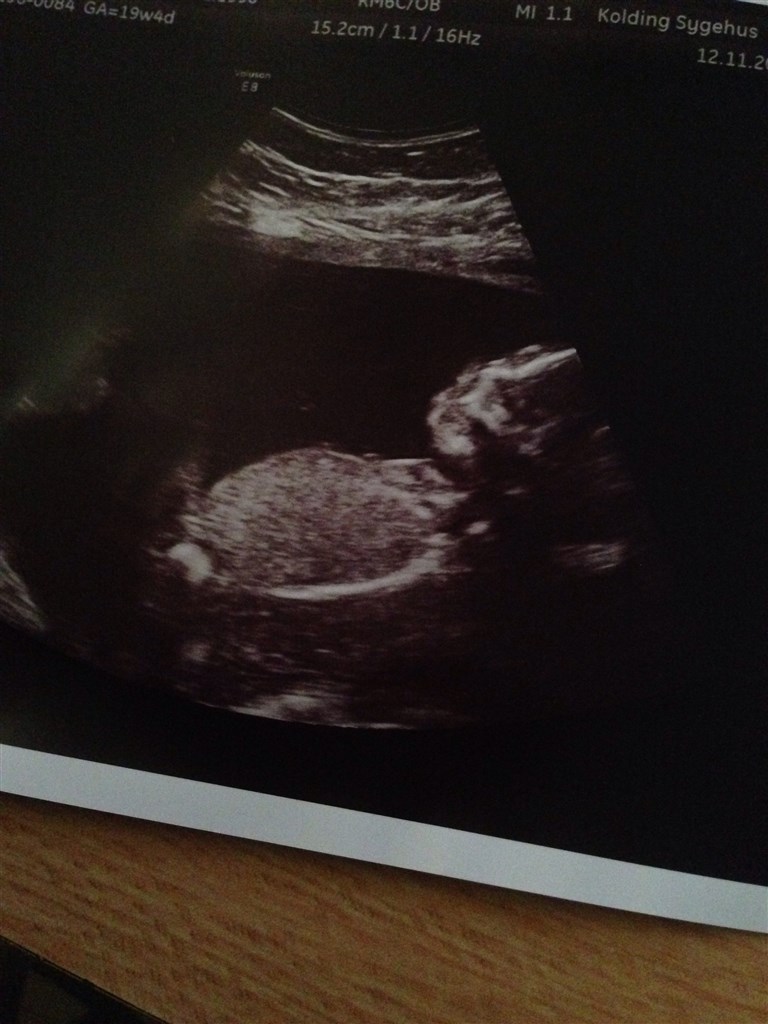

Jeg sidder her og ser overs skønne skannings billeder igennem, og ser så denne her hvide runde kugle på billederne for enden af maven, hmm hvad kan det være? En hånd eller måske et par kugler? Min kæreste er sten sikker på det er en pige... Men kommer i tvivl hvergang jeg sidder og ser disse billeder. Nogle som kan forklare? (:

trooor det er hånden men ved sgu ikke.

det ligner det der også var/er på nogle af scanningsbillederne fra min datter og der sagde hun at det var en "fedtplet" eller en form for pixelsfejl i deres printer...

Jeg ser det samme på min datters scanningsbilleder og der sagde hende der scannede mig at det var hendes hofteben